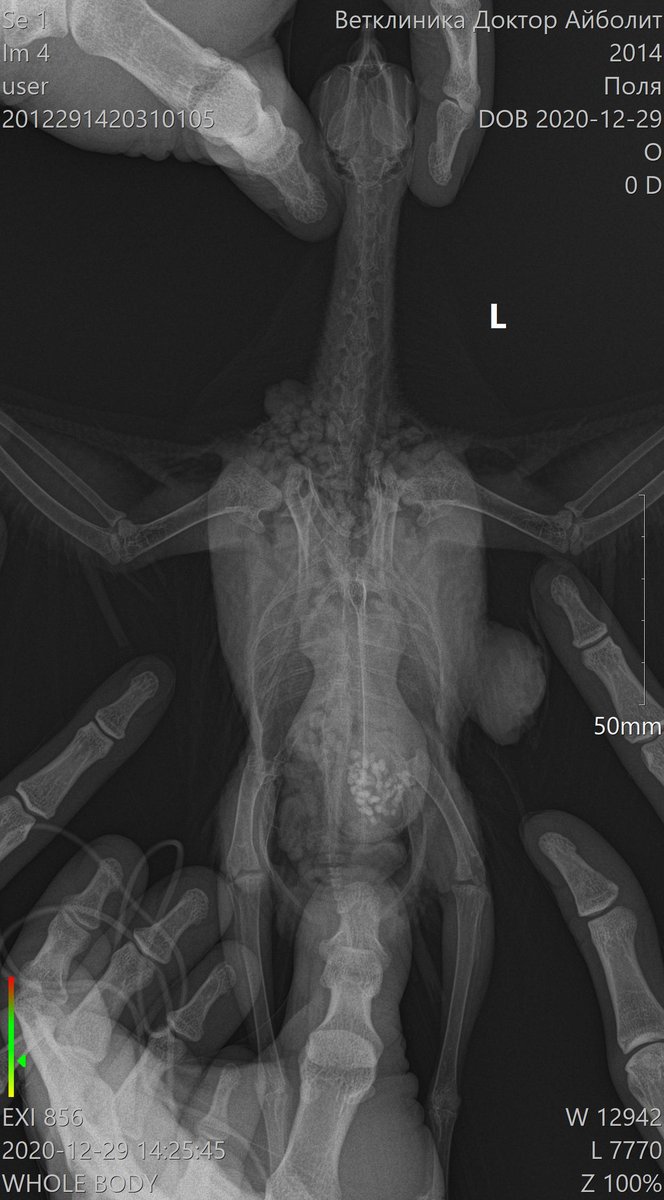

Lia V Опубликовано 30 декабря, 2020 Автор #25 Опубликовано 30 декабря, 2020 Добрый вечер, как обещала, рассказываю о результатах похода к хирургу. Вчера сделали операцию моему красавцу. Он, мягко говоря был сильно удивлен, сказал, что ранее такого не встречал. Приложу фото, которое он сделал во время операции. Этих шишек было 2, размеры и скорость роста шокируют (((((((((( одну хорошо видно на рентгене, вторая была на крыле (на плече, она была меньше, скрыта в перьях и не так заметна, на фото именно она). Природа этих наростов не ясна((((( Гистология будет готова только через 21 день. Назначили пить амоксиклав, флуконазол, гепатовет, кальция глюконат, транексам, ветом. Завтра записалась на контрольный повторный прием к орнитологу. Попрошу ее дотошно его с ног до ушей осмотреть (у меня это получается плохо, он вертится, я все время боюсь, что швы разойдутся и не рискую его сильно крутить. У врача, естественно, это получается ловко и умело). По цене операция + 2 проекции рентгенографии и гистология вышли в 7.300 руб. Сидит мой Поля с собранным крылом, в воротнике, летать не пускаю, гуляет только по клетке. Скучно ему. От избытка энергии чистится как дурной (ему больше реально и делать нечего), воротник спасает лишь частично, я все переживаю как бы не расковырял раны. Честно говоря, у меня паника и ощущение полой неопределенности. Спасибо врачам огромное, но ситуация все равно пока не ясная совершенно. Встречалась ли Вам такая ситуация??? Что это может быть???

Zosia Опубликовано 30 декабря, 2020 #26 Опубликовано 30 декабря, 2020 Меланома или меланоцитома. Встречались, конечно... Кроме всего прочего у птицы гипертрофия сердечной мышцы, дилатированное сердце. Есть так же некие объекты по верхней границы печени (в ВД проекции) и справа (для смотрящего на снимок- слева) https://public.fotki.com/Shemlik/cancer/operacia001.html https://public.fotki.com/Shemlik/cancer/55.html https://public.fotki.com/Shemlik/cancer/59.html#media https://public.fotki.com/Shemlik/cancer/05-09-20-002.html https://public.fotki.com/Shemlik/cancer/05-09-20-001.html#media